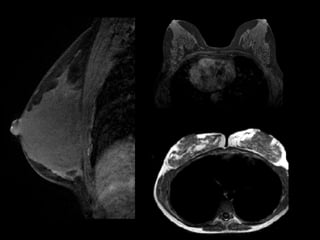

54 anos

Carcinoma ductal invasivo unifocal na mamografia e US

Estadiamento localInformações clínicas relevantesDetecção de focos tumorais ocultos na mamografia e na USModificação na terapia cirúrgicaRedução na taxa de recidiva e aumento na sobrevida?